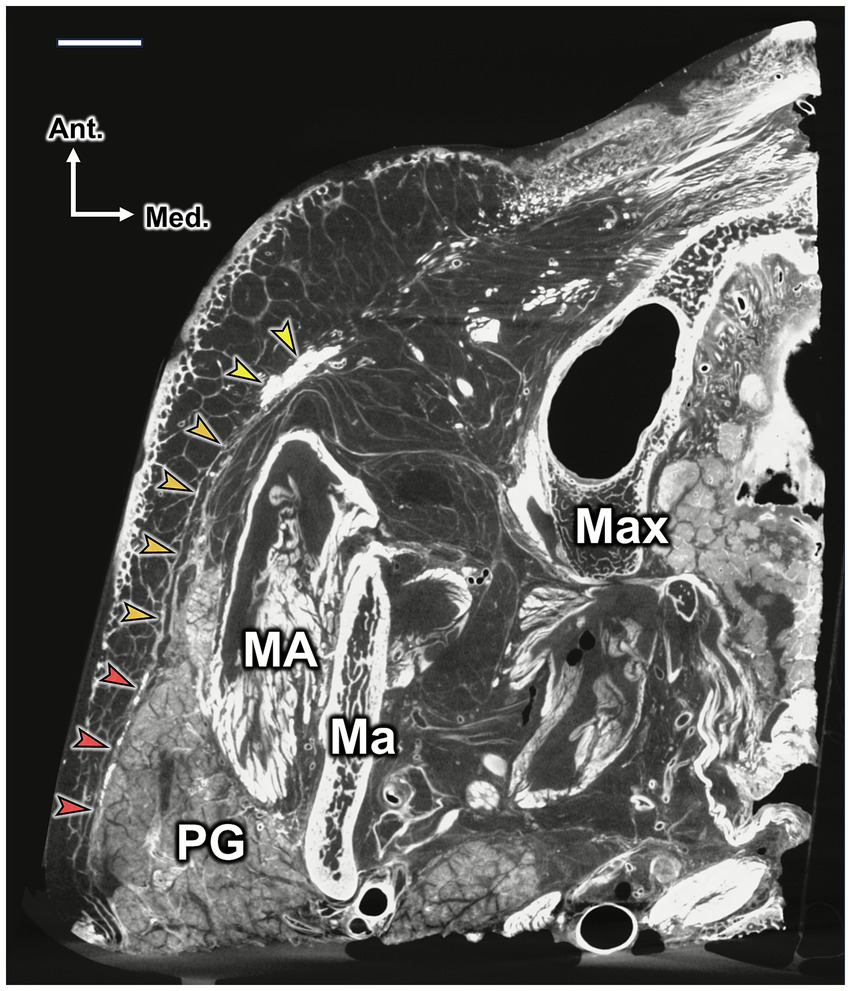

Figure 3

Micro-CT image showing the SMAS layer and its connections with the platysma and zygomaticus major and minor muscles. The image was taken at the level of the nasal ala. The red, orange, and yellow arrowheads indicate the platysma, SMAS, and zygomaticus major and minor muscles, respectively. Note that the platysma and SMAS cover the parotid gland (PG) and part of the masseter muscle (MA), with limited space between the SMAS, PG, and MA. Scale bar: 1 cm; Ma, mandible; Max, maxilla; Lat., lateral; Med., medial; Ant., anterior; Post., posterior.